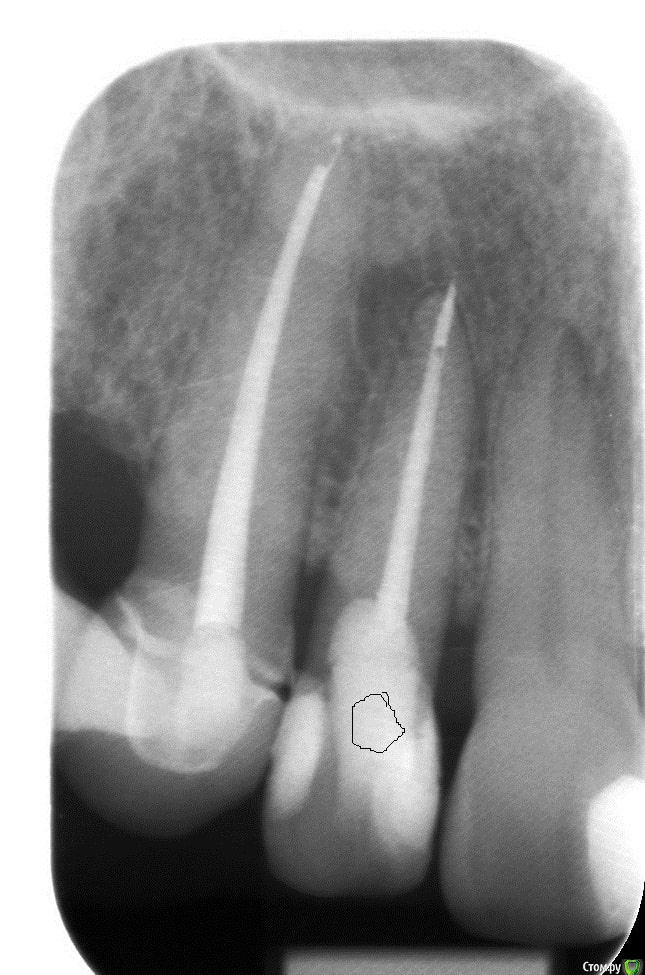

ellenchik Опубликовано 9 января, 2020 Автор Поделиться Опубликовано 9 января, 2020 Добрый день, уважаемые Доктора.Я снова к Вам за советом. После отпуска ( Перемена климата -прилетела из +25 в +2 град.) уже неделю болит уже другой передний зуб под коронкой (канал пролечен 4,5 г. назад) Болит очень высоко с внешней стороны десны в самом вверху. Особенно при нажатии точки прямо под правой ноздрёй носа. Боль жгучая,ноющая. С нёбной стороны никаких болевых ощущений. Временами такая "гуляющая" боль по передним верхним зубам. Врач сделал снимки и сказал, что надо делать резекцию верхушки корня у этого зуба и заодно у рядом стоящего зуба (по моему клык) с пролеченным каналом. Еще он где-то увидел трещину.В рот заглянул,но зубы ни на какие реакции не проверял. На снимках причинный зуб (по моим ощущениям ) с "кривым кружочком"Буду очень признательна за советы. Действительно все так плохо по снимкам и необходима резекция обоих зубов? Или есть другие варианты. И на каком зубе видна трещина? С уважанием ЕленаP.S-Прикрепляю на всякий случай старый снимок ( третий по счету ) этих зубов после лечения в 2015 г. Ссылка на комментарий

ellenchik Опубликовано 10 января, 2020 Автор Поделиться Опубликовано 10 января, 2020 Посмотрите ,пожалуйста снимки. Что можно по ним сказать?К кому лучше с этим обратиться, к хирургу или эндодонтисту?У меня еще и в понедельник 13.01 запланирована небольшая операция,отменить нельзя. (не с зубами связано) 1)Можно ли отложить лечение зуба на неделю?2). может пока Антибиотики? С уважением Елена Ссылка на комментарий

ellenchik Опубликовано 12 января, 2020 Автор Поделиться Опубликовано 12 января, 2020 Посмотрите ,пожалуйста снимки. Что можно по ним сказать?К кому лучше с этим обратиться, к хирургу или эндодонтисту?У меня еще и в понедельник 13.01 запланирована небольшая операция,отменить нельзя. (не с зубами связано) 1)Можно ли отложить лечение зуба на неделю?2). может пока Антибиотики? С уважением Елена Ссылка на комментарий

ellenchik Опубликовано 12 января, 2020 Автор Поделиться Опубликовано 12 января, 2020 Если мои снимки малоинформативны,подскажите плиииз... Сделаю новые.Но всё же надеюсь Ваши мнения по поводу резекции корней. Очень нужен компетентный взгляд со стороны. Может есть другие варианты и не так всё критично по снимку. Буду очень признательна. Ссылка на комментарий